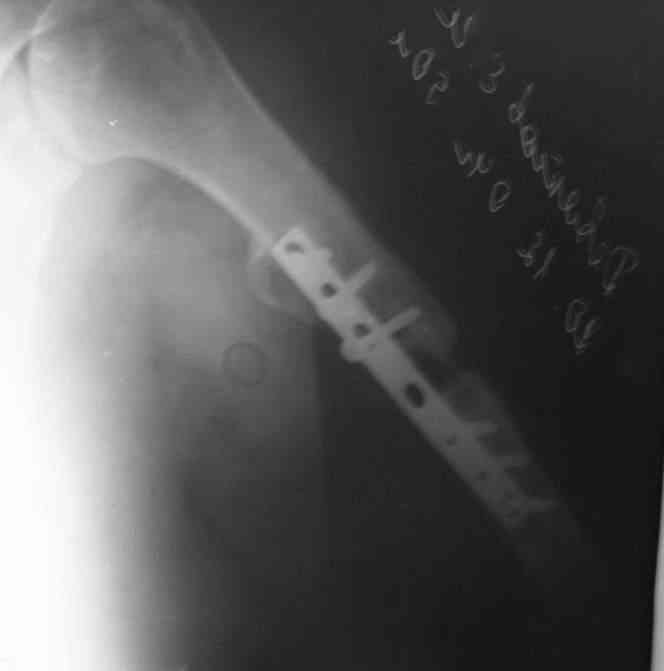

Есть вариант открытого вмешательства с резекцией зоны ложного сустава, костной пластикой и накостным остеосинтезом хорошей пластиной, в смысле мощной и длинной.

>A.Ch< Есть вариант открытого вмешательства с резекцией зоны ложного сустава, костной пластикой и накостным остеосинтезом хорошей пластиной, в смысле мощной и длинной.

Вряд ли для больной с ожирением и астмой большая травматичная операция с большим риском вослеоперационной нейропатии лучевого нерва является лучшим выходом...

Уважаемые коллеги! Большое спасибо за советы, да еще и с иллюстрациями. Наша частная клиника ортопедотравматологического профиля имеет все необходимое для накостного остеосинтеза, но современный интрамедуллярный остеосинтез нам пока не доступен. Предполагаю: предложить больной и далее жить, пользуясь ортезом, а в случае отказа, не рисковать и отправить на лечение в другое лечебное учреждение. К нам больная претензий не имеет, лучевой нерв не поврежден. Достойно и гарантировано помочь не сможем, поскольку я склоняюсь к эндопротезированию диафиза.